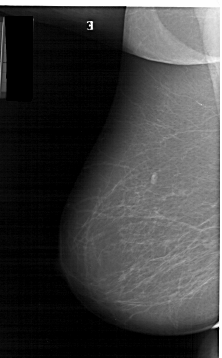

A_1159_1.LEFT_MLO

LEFT_MLO LINES 6436 PIXELS_PER_LINE 3991 BITS_PER_PIXEL 12 RESOLUTION 43.5 NON_OVERLAY